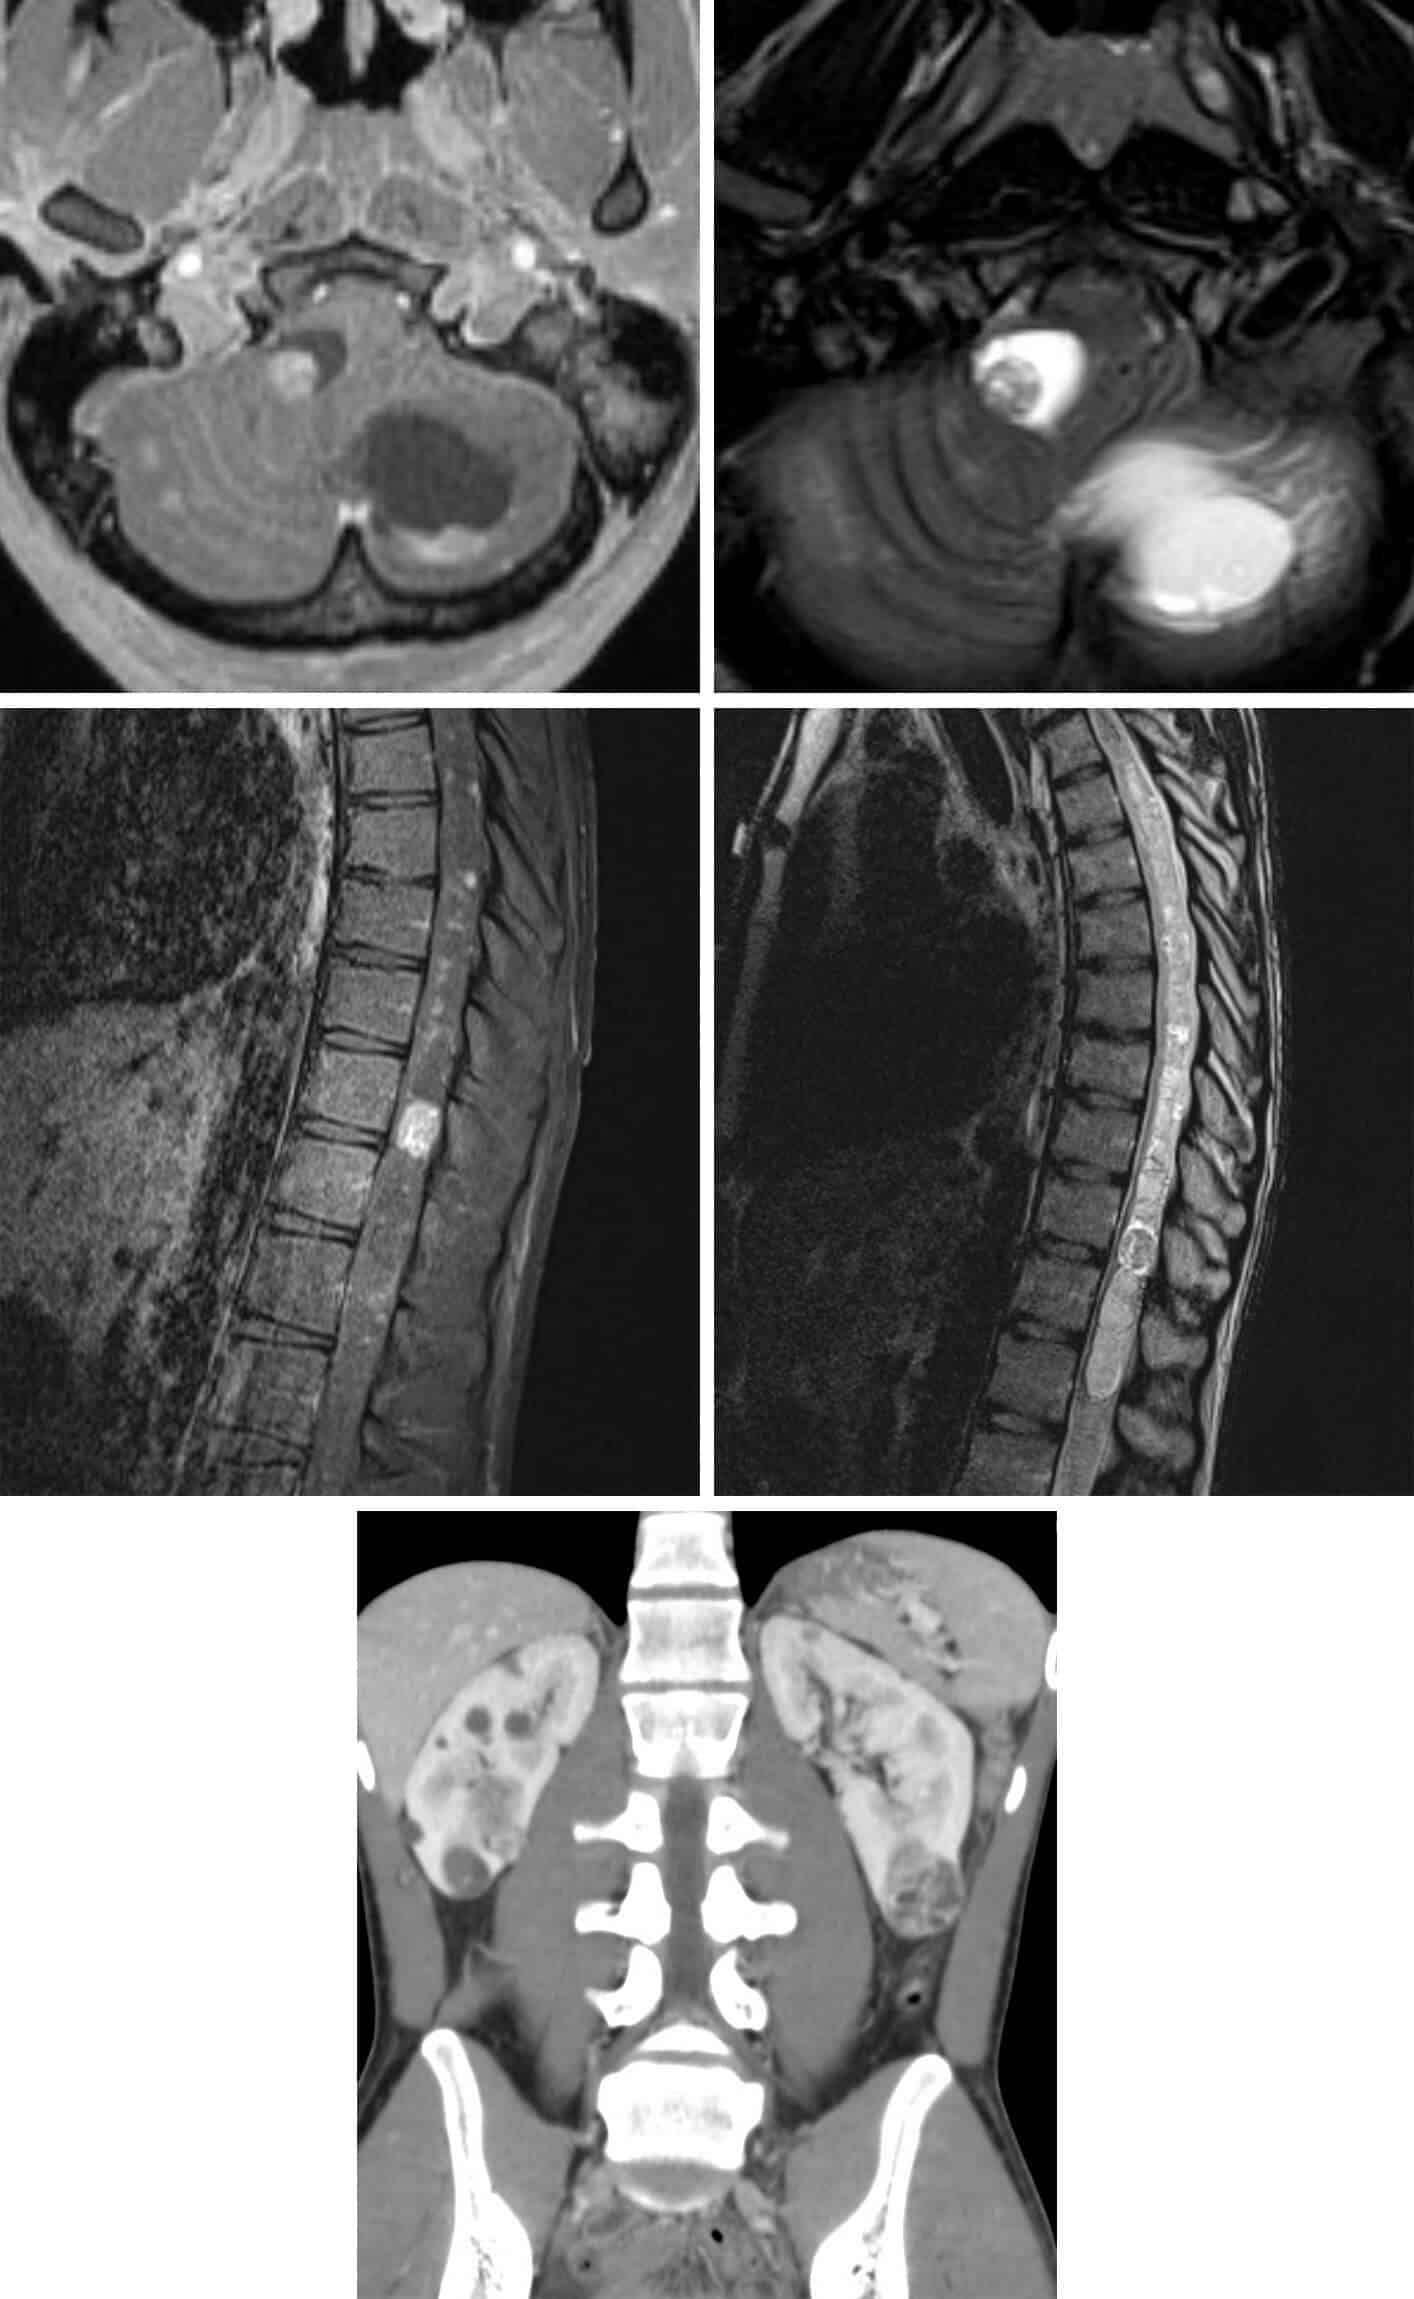

Chẩn đoán u trong ống sống thường dựa vào các phương pháp hình ảnh học và có thể bao gồm:

- Chụp cộng hưởng từ cột sống (MRI): MRI là công cụ quan trọng để đánh giá các mô mềm như tủy sống và các rễ thần kinh. Nó tạo ra hình ảnh 3D giúp bác sĩ xác định vị trí và kích thước của khối u, cũng như sự ảnh hưởng của nó đến các cấu trúc xung quanh.

- Chụp cắt lớp vi tính cột sống (CT): CT tạo ra các lát cắt chi tiết của cột sống, giúp xác định hình dạng và kích thước của khối u. Phương pháp này có thể hỗ trợ trong việc đánh giá cấu trúc của ống sống và các thành phần bên trong.

Ngoài các phương pháp trên, bác sĩ có thể yêu cầu các xét nghiệm hình ảnh khác như chụp CT ngực bụng, chụp X quang ngực, và PET-CT để xác định khả năng di căn của khối u.